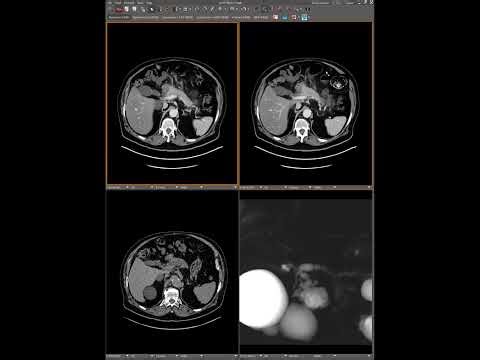

Illustrative Case Presentation #1 | …